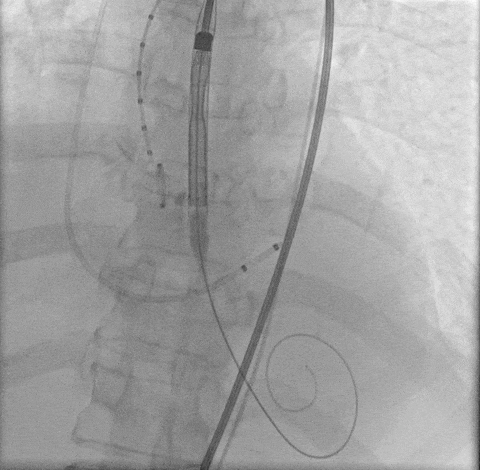

最终定位

最终释放

瓣膜稳步脱钩后,造影显示瓣膜位置合适,冠脉灌注良好,无瓣周漏。

稳步脱钩

最终造影